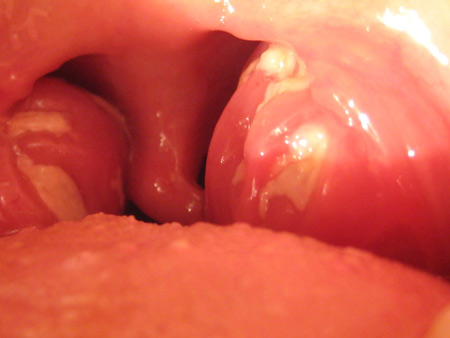

Хронічний тонзиліт має різні форми, але, як правило, його симптоми впізнавані. У хворого з’являється сильний біль у горлі, що посилюється при ковтанні і мови, підвищується температура. Мигдалики збільшуються в розмірі, червоніють, на них чітко видно гнійнички. Також може виникати сухість у роті, головний біль, втома.

Лікар при огляді горла легко може поставити правильний діагноз, знаючи, як виглядає тонзиліт. Запідозрити тонзиліт можна за зовнішніми ознаками мигдаликів:

- мигдалики виглядають разрыхленными і ущільненими;

- на мигдалинах спостерігається біло-сірий наліт, може бути згусток гною;

- опухлий язичок в гортані;

- розміри мигдалин збільшені;

- сильне почервоніння всього горла;

- хронічний процес видають рубці і спайки на гортані;

- шийні лімфовузли збільшені, болючі на дотик.

На слизовій оболонці мигдаликів можна виявити розпушення, почервоніння, наявність гнійних скупчень, спайки і рубці. У період загострення горло виглядає набряклим, запалених, червоним, мигдалики збільшуються, і присутній білий або сірий наліт. Порушення носового дихання тільки погіршує загальне самопочуття пацієнта.

На фарингоскопії виявляється гіперемія, потовщення країв і набряк піднебінних дужок. Можливо зрощення піднебінних дужок з трикутної складкою і мигдалем. Нерідко спостерігається розпушення мигдаликів (особливо у дітей). У лакунах мигдаликів міститься гній, іноді з неприємним запахом. Часто виявляється збільшення регіонарних лімфовузлів.